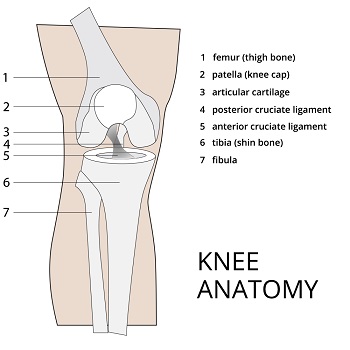

Knee Joint Preservation

The knee joint, the largest in the human body, serves as the vital connection between the lower leg and thigh. It shoulders the responsibility of supporting the body's weight in both horizontal and vertical directions. The knee's complexity arises from its composition of essential components, including bones, cartilage, ligaments, and tendons, rendering it susceptible to a range of injuries due to its critical role in our daily lives.

The biomechanics includes knee realignment and ligament reconstructions of the knee. Correction of misalignment improves biomechanics by correcting bowing or knocked knee deformities of the knee and this reduces loads on certain parts of the knee joint reducing pain. The biological forms of treatment are cartilage repair techniques that include Autologous Chondrocyte Implantation (ACI) and osteochondral allograft transplant (OATS).

With the ACI procedure, cartilage cells are harvested from a non-weight bearing area of the knee and grown in a laboratory, and then implanted in the area of the cartilage defect/injury.

With the OATS procedure, autograft cartilage is used and it is obtained from the patient themselves from the non-weight bearing part of the articular cartilage. The allograft can be shaped to fit the cartilage defect and is pressed fit into place.

During the osteotomy procedure, two small incisions are made, through which a camera is passed to allow the surgeon to assess the damage. An incision is made above the tibia so that the bone can be cut, to allow the realignment of the knee so that the patient’s weight is transferred to the healthier side of the knee joint. The procedure takes up to two hours.